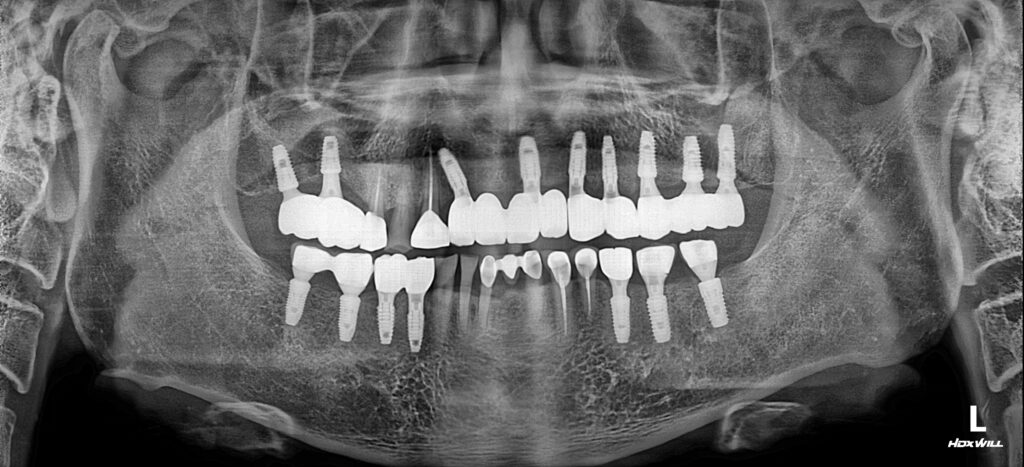

25.06.23

약 1년의 치료기간 후 모든 치료가 성공적으로 마무리된 모습입니다. 다수의 임플란트 식립을 진행하셨기 때문에 전체적인 교합을 맞추며 진행하는 것이 어려운 사례였으나 환자분과의 긴밀한 소통을 통해 잘 마무리할 수 있었습니다.

환자분께서 걱정이 많으셨는데 영도치과 서울화이트S치과의 섬세한 배려로 편안하게 치료받고 식사와 심미적으로도 만족하는 결과가 나온 것 같다고 고맙다고 해주셨습니다:)